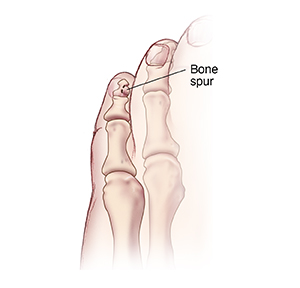

Toe spur

Removing a toe spur involves making only a small skin incision. A tiny power rasp (similar to a dental burr) or a special file is inserted to smooth the bone. After surgery, your foot will be bandaged. But you can often walk on it right away. In some cases, you may need to wear a surgical shoe for a few weeks.